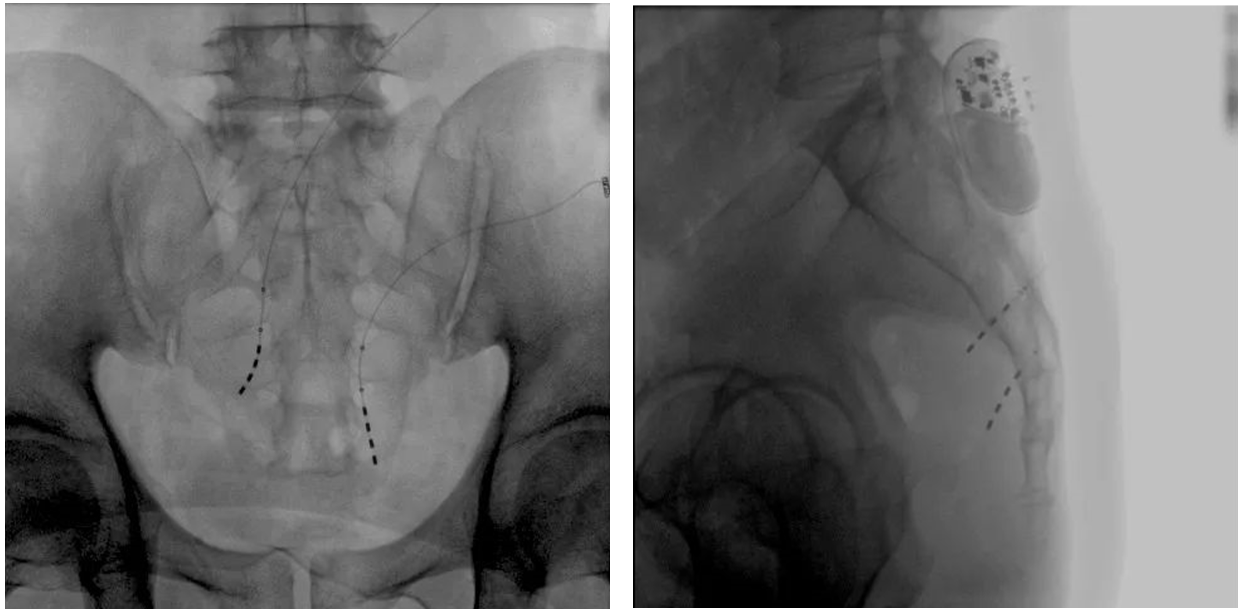

該患者兩年前被診斷患有膀胱過度活動癥(OAB),出現(xiàn)嚴重尿頻、尿急、尿細線等癥狀,醫(yī)生為其做了骶神經(jīng)調(diào)控手術。近期,患者癥狀又開始加重,生活質(zhì)量受到影響,為減輕癥狀,改善生活,患者前往南醫(yī)大二附院就診。衛(wèi)中慶主任及其團隊在查看患者病情后,決定重新調(diào)整電極刺激位置,將刺激點由原左側(cè)骶4神經(jīng)孔改為骶3神經(jīng)孔,通過新的神經(jīng)調(diào)節(jié)順利地改善了癥狀。

患者術前影像

大平板一體式移動C形臂術中影像

在骶神經(jīng)調(diào)控術或者骶神經(jīng)刺激術(SNS)中,醫(yī)師首先會在透視引導下把電極通過導針插入到骶3神經(jīng)孔位置,通過脈沖電流的刺激,達到興奮神經(jīng)纖維并抑制逼尿肌收縮。在這一步,醫(yī)師會先對患者的神經(jīng)刺激反應做測試評估,如果刺激效果明顯,說明該方案能夠達到手術預期。接下來醫(yī)師會在附近皮下脂肪處植入一塊脈沖電流發(fā)生器并與電極相連,使該部位今后能得到長期的電刺激,改善OAB癥狀。